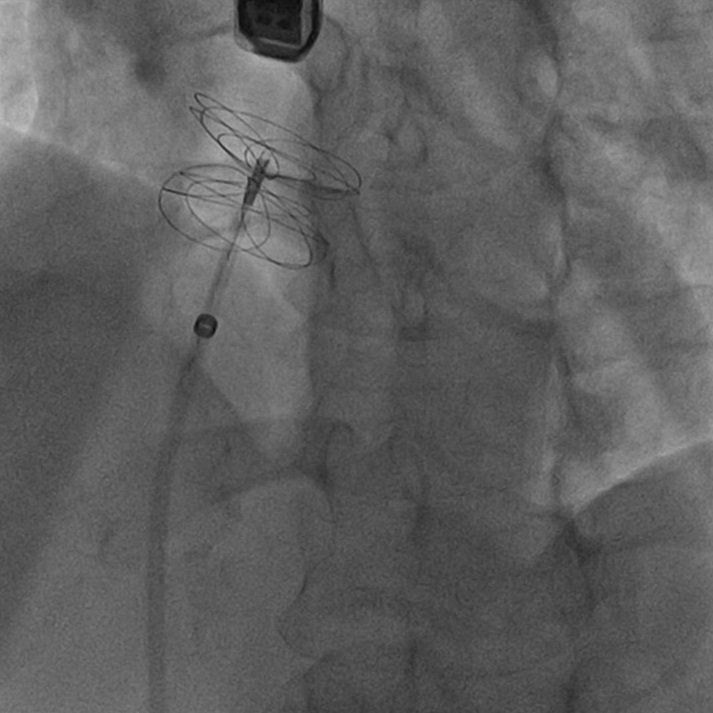

Dal 2010 al pensionamento è stato responsabile dell’unità di Emodinamica dell’Ospedale di Lecco, ove nel corso degli anni, oltre all’angioplastica coronarica, sono stati intrapresi anche più complessi trattamenti trans-catetere di cardiopatie strutturali: sostituzione aortica trans-catetere (TAVI), trattamento trans-catetere della mitrale ed interventi di chiusura di pervietà del forame ovale (PFO), difetti interatriali (DIA), difetti interventricolari (DIV) e dell’auricola sinistra ecc.